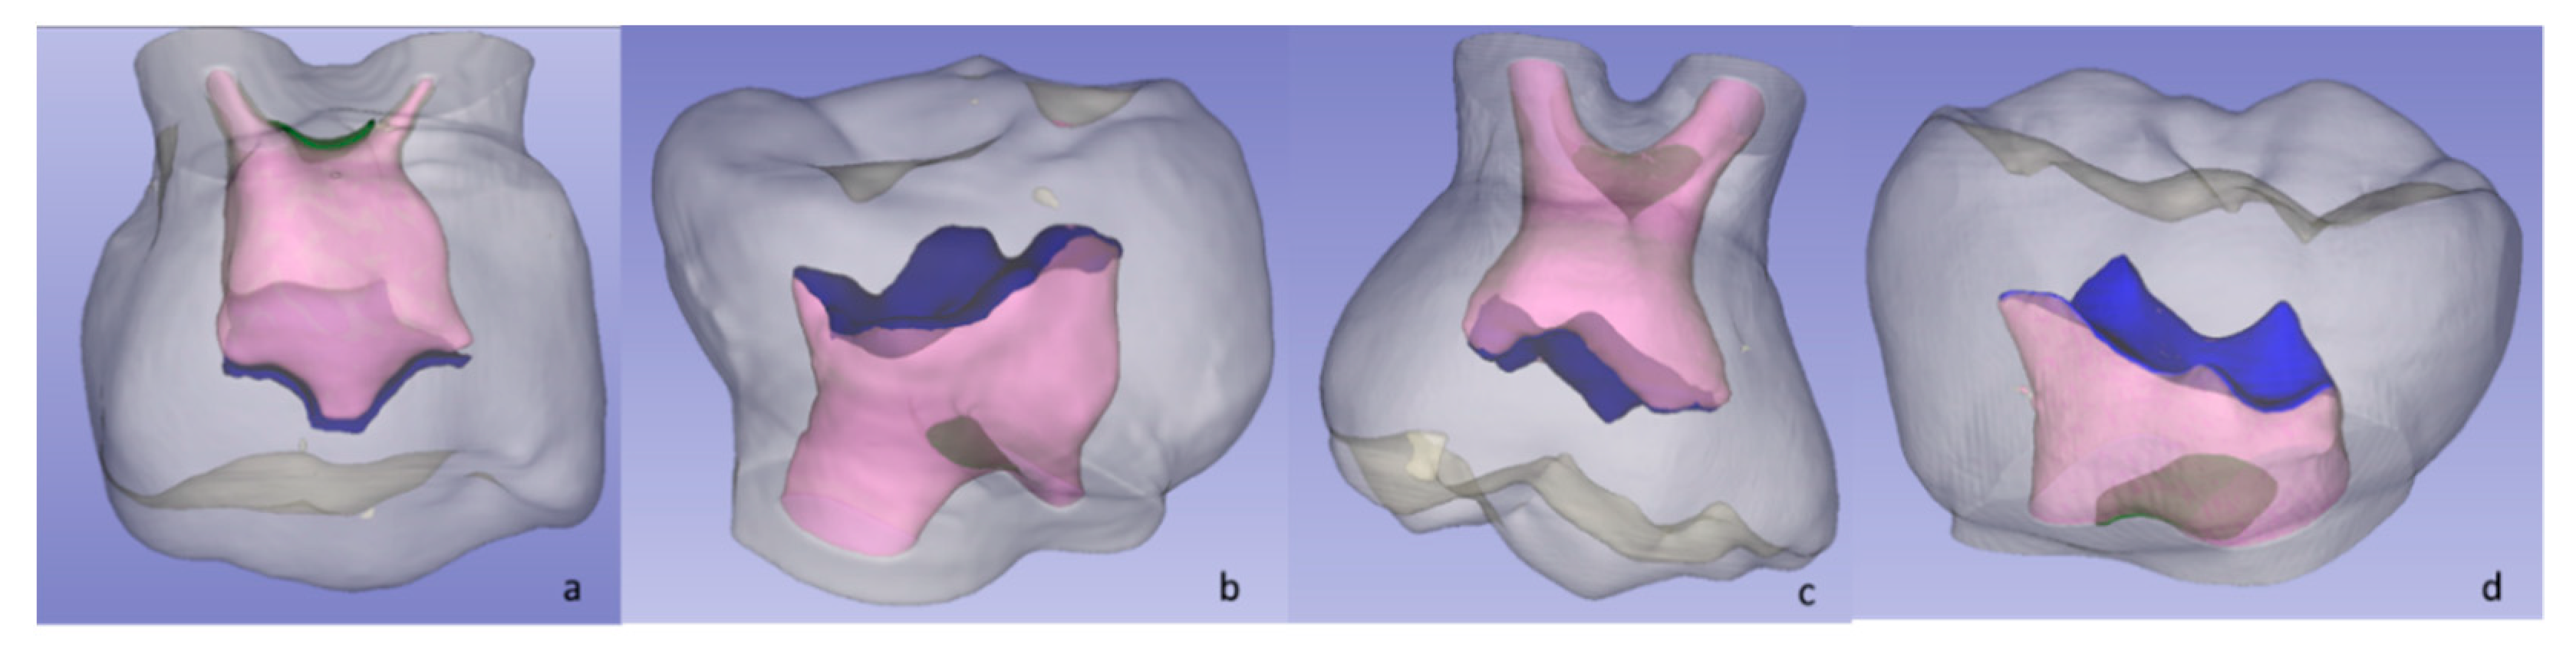

2.4.1. Pulp Chamber Roof (PCR) and Pulp Chamber Floor (PCF)

2.4.3. Pulp Chamber Volume (PV), Dental Crown Volume (CV), and Volume Ratio (VR)